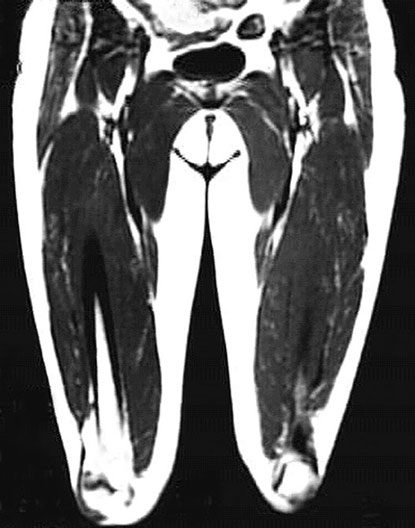

Thigh Coronal View

*No labels on this image